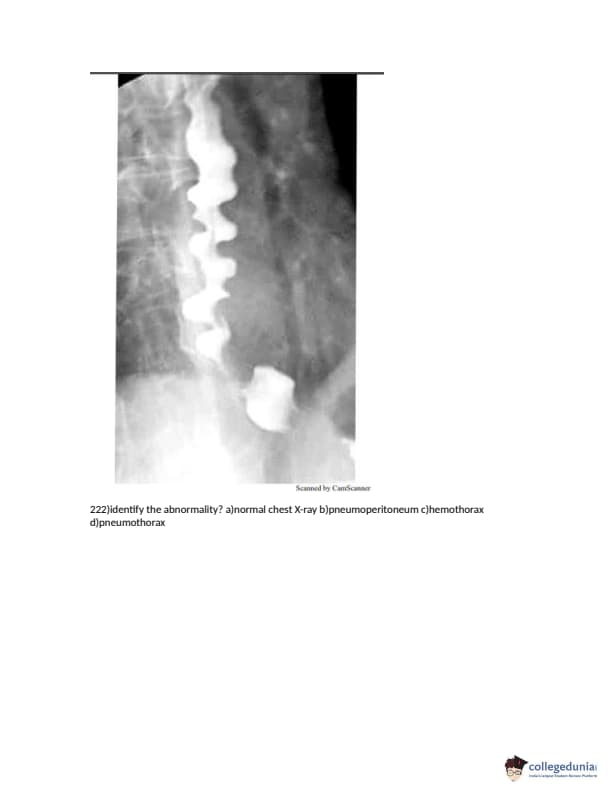

FMGE 2018 Question paper with answer key pdf conducted on December 14, 2018 is available for download. The exam was successfully organized by National Board of Examinations (NBE). The question paper comprised a total of 226 questions.